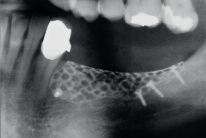

Augmentation 19 | Wundverschluss nach Implantation 20 | Wundheilung 1 0 Tage postoperativ 21 | Aufnahme 6 Monate nach Implantation Verlauf des Nervs ca 1 mm unterhalb der Implantate 18 | Abdeckung mit Geistlich Bio Gide® und PRF Matrix > Trotz

Bio Gide® | 30 x 40 mm 10 | Zusätzliche Anwendung von PRF Matrizes auf die GBR Membran Geistlich Bio Gide® zur Unterstützung der Wundheilung 11 | Primärverschluss durch mehrschichtige, spannungsfreie Wundnaht 12 | Verlauf der Wundheilung nach 1 Woche 13 | Radiologischer Befund für die Implantat planung 14 | Freilegung des Gitters durch Schnitt führung in der alten Narbe 15 | Rekonstruierter Kieferkamm nach Gitter entfernung 17 | Implantate in situ mit anschließender Nachkonturierung mit Geistlich Bio Oss® 16 | Ausreichendes Knochenangebot, um Im plantate mit hoher Primärstabilität zu setzen